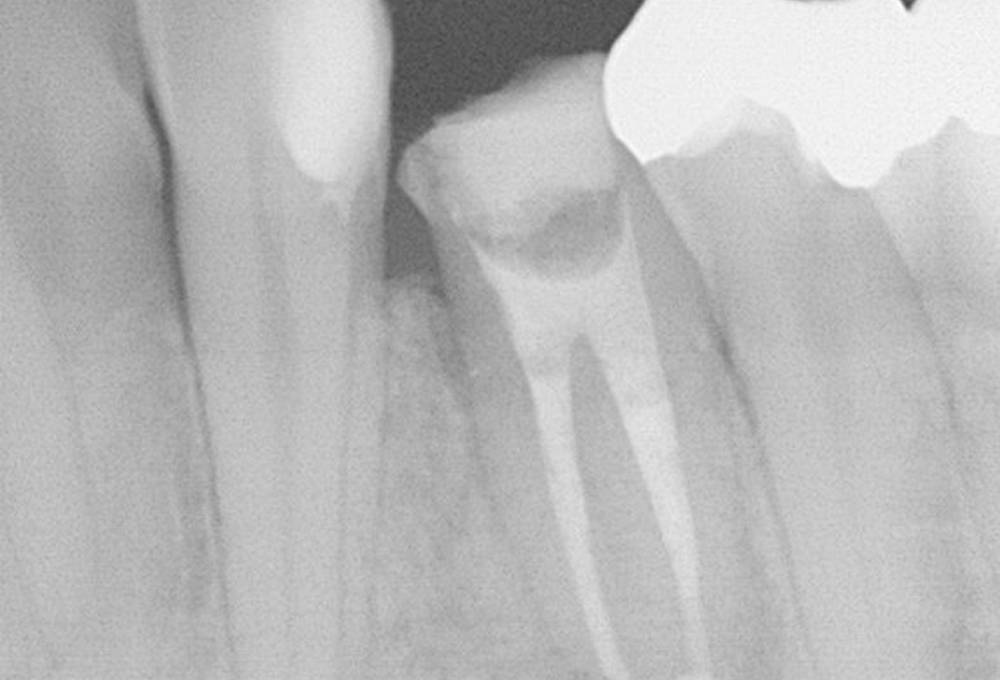

②術後 感染根管処置後MTAにて根管充填 病変も縮小した